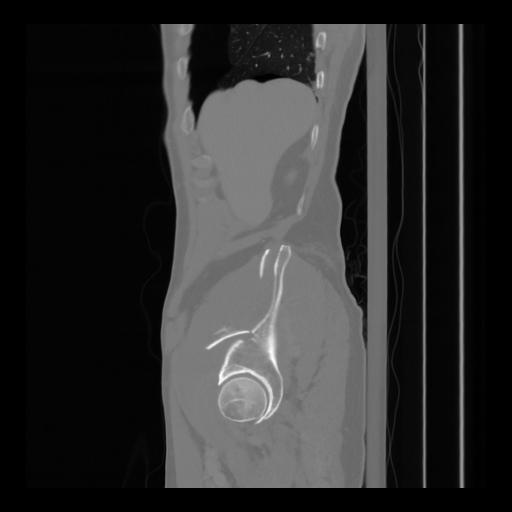

36 CUERPO,CE,Sagittal,3.000,CUERPO,Sagittal,